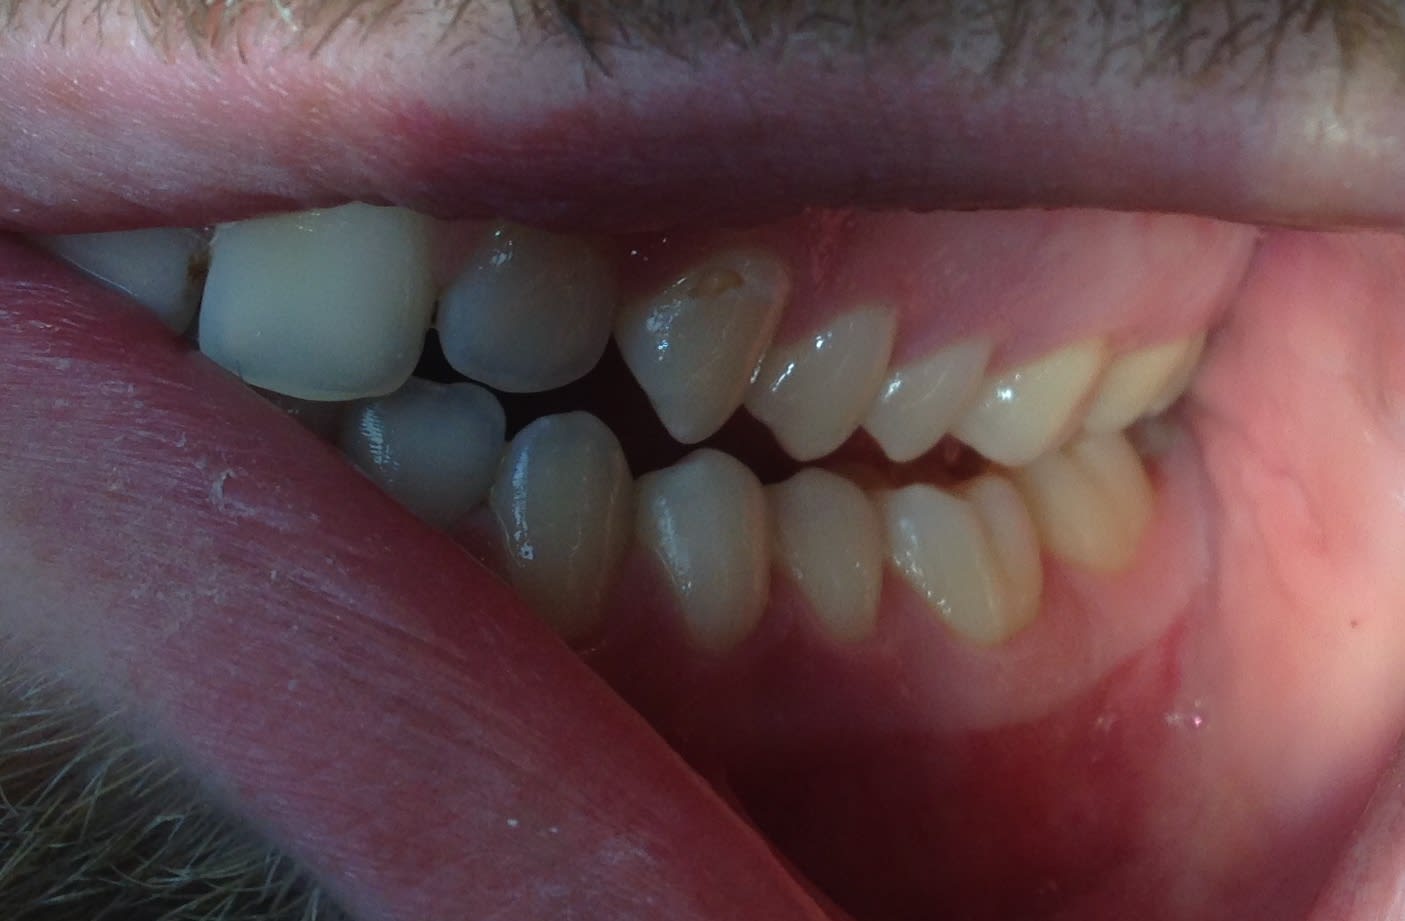

regardez moi ça cette 6 sur Implant réalisée par les chinois que je viens de poser : c'est pas beau ça quand même ? Vraiment Du bon travail. Et juste à coté regardez les CCM réalisées par sans doute des prothésistes français. Y a pas photo : une très nette supériorité en qualité pour les prothésistes chinois.

Quoique ces couillons ne m'ont pas fait de pont d'email, et la cuspide MP devait être plus grosse que la D... j'ai même pas remarqué ça hier 😊 . En même temps,Entre nous c'est pas ça qui va changer grand chose à l'efficacité masticatoire. Ils ont du filer cette 6 au mec qui s'occupe des 6 mandibulaires au lieu de Le donner au mec qui s'occupe des 6 maxillaires .